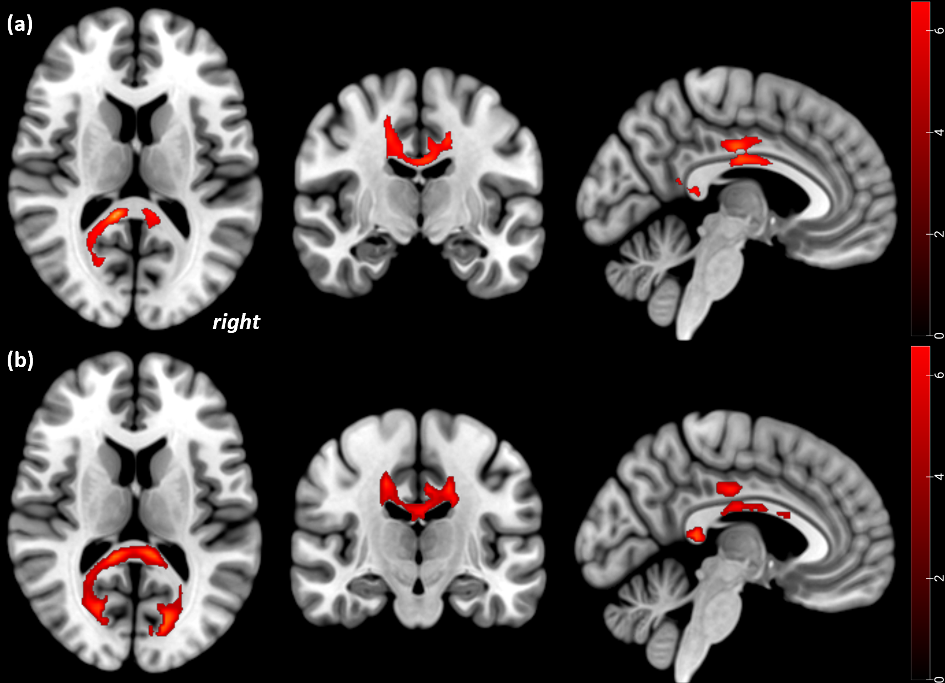

Fig. 1:Statistical parametric mapping (t) intensity projection maps rendered onto a stereotactically normalized MRI scan, voxel cluster of the significant FA alterations in AN (statistical significance is thresholded at p < 0.001, FWE p < 0.05 corrected at the cluster level). FA decreases in acute AN patients with attachment trauma relative to HC at Tp1 (a), and at Tp2 (b). The right side of the image corresponds to the right side of the brain (Gander et al., 2023)

- Gander, M., Lenhart, L., Steiger, R., Buchheim, A., Mangesius, S., Birkl, C., Haid-Stecher, N., Fuchs, M., Libal, A., Dabkowska-Mika, A., Gizewski, R. & Sevecke, K. (2023). Attachment trauma is associated with white matter fiber microstructural alterations in adolescents with Anorexia Nervosa before and after exposure to psychotherapeutic and nutritional treatment. Brain Sciences, 13 (5), 7. doi: 10.3390/brainsci13050798